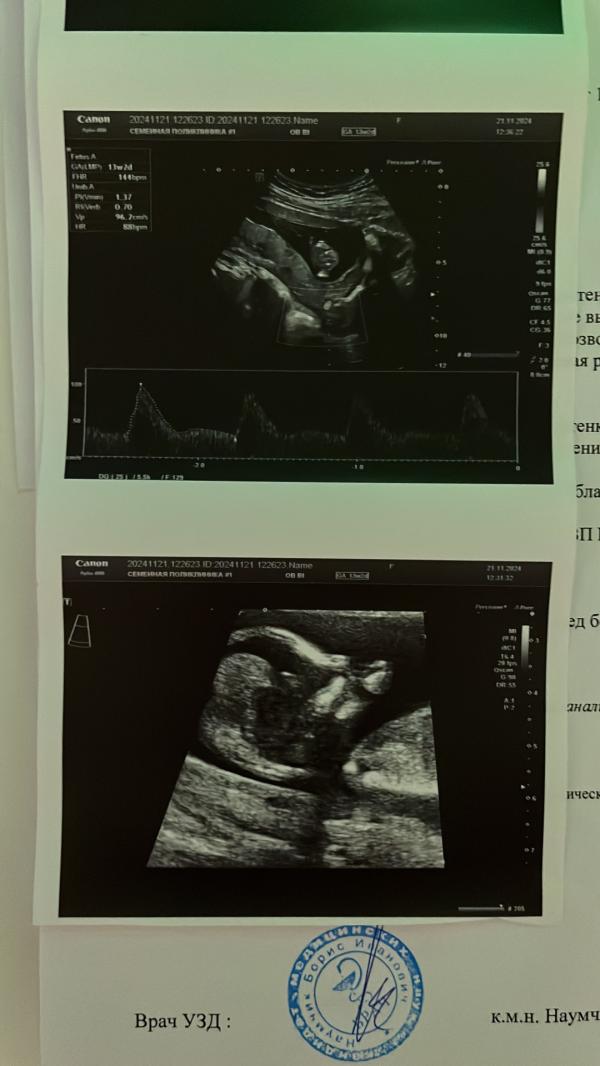

Сегодня была на первом скрининге))) 13 неделю 1 ден ❤️. Мой ребеночек пальчики сосет из-за того что мама его (её) не кормила